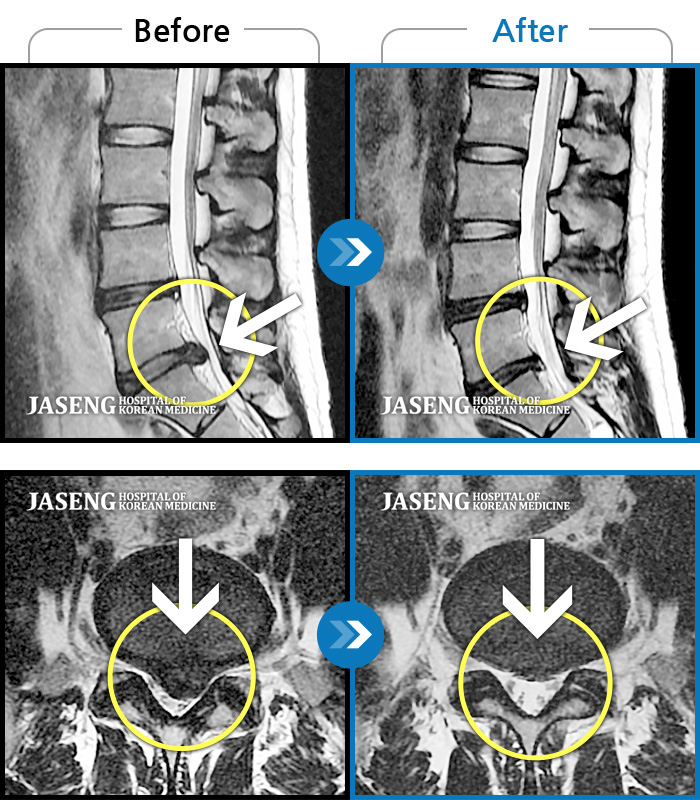

수술을 해야 하는 상황이었는데 자생 한방 병원의 김유진 원장님 덕분에 현재 수술없이 잘 치료를 받고 있습니다.

처음에 수술없이 완쾌할수 있을까 걱정을 많이 했지만 지금은 완쾌할수 있을거랑 희망을 가지고 통원치료를 받고 있습니다.